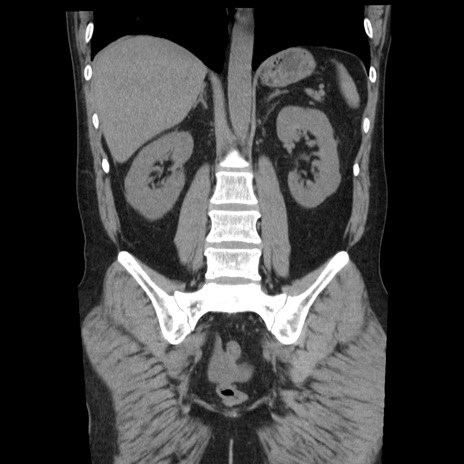

症例29(冠状断像)

【症例】40歳代男性

【現病歴】2日前から胃痛あり。徐々に周期的な激痛に変化した。本日になっても激痛があるため受診。

【身体所見】意識清明、BT 38-39℃台あり、腹部:膨満、やや硬、右下腹部に圧痛あり。

【データ】WBC 8500、CRP 23.26